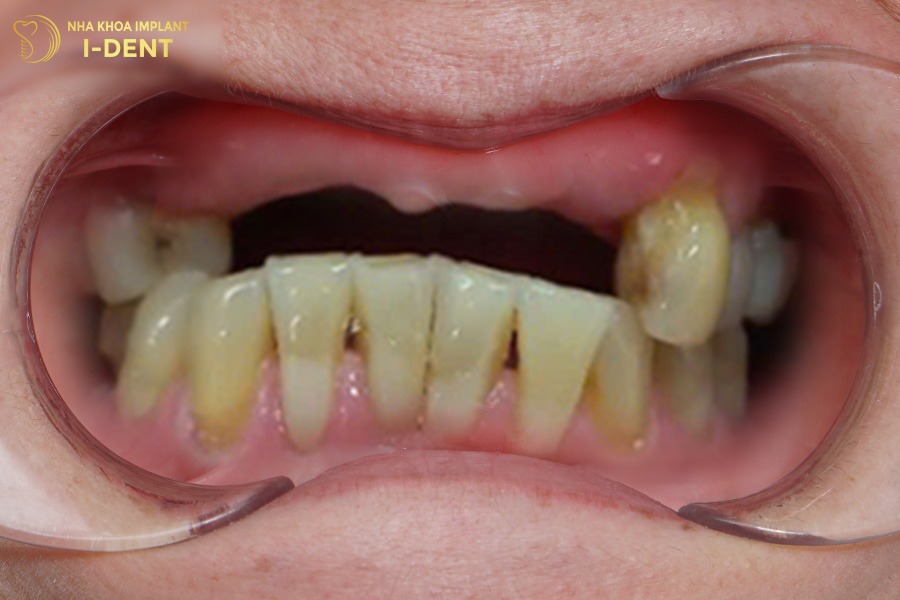

Vì chủ quan trong việc chăm sóc răng miệng, thêm thói quen hút thuốc khiến chú Nguyễn Hải mắc bệnh lý viêm nha chu nặng. Lâu ngày gây tiêu xương và làm lung lay, gãy rụng răng gần hết cả 2 hàm.

Tình trạng răng ban đầu của chú Nguyễn Hải

Với tình trạng này, bác sĩ Tín đã tiến hành điều trị nha chu và nhổ các răng lung lay để ngăn ổ nhiễm trùng lan rộng trước. Sau đó chỉ định phương án cấy ghép Implant All-on-4 cho cả hai hàm, đặt 4 trụ Implant cho 1 hàm và phục hình 12 răng sứ lên trên, nhằm đảm bảo thẩm mỹ cũng như chức năng ăn nhai chắc chắn cho chú.

Sau khi có răng mới, chú Hải không còn phải chịu đựng tình trạng đau nhức răng và khó ăn nhai, sức khỏe của Chú cũng được cải thiện hơn rất nhiều.